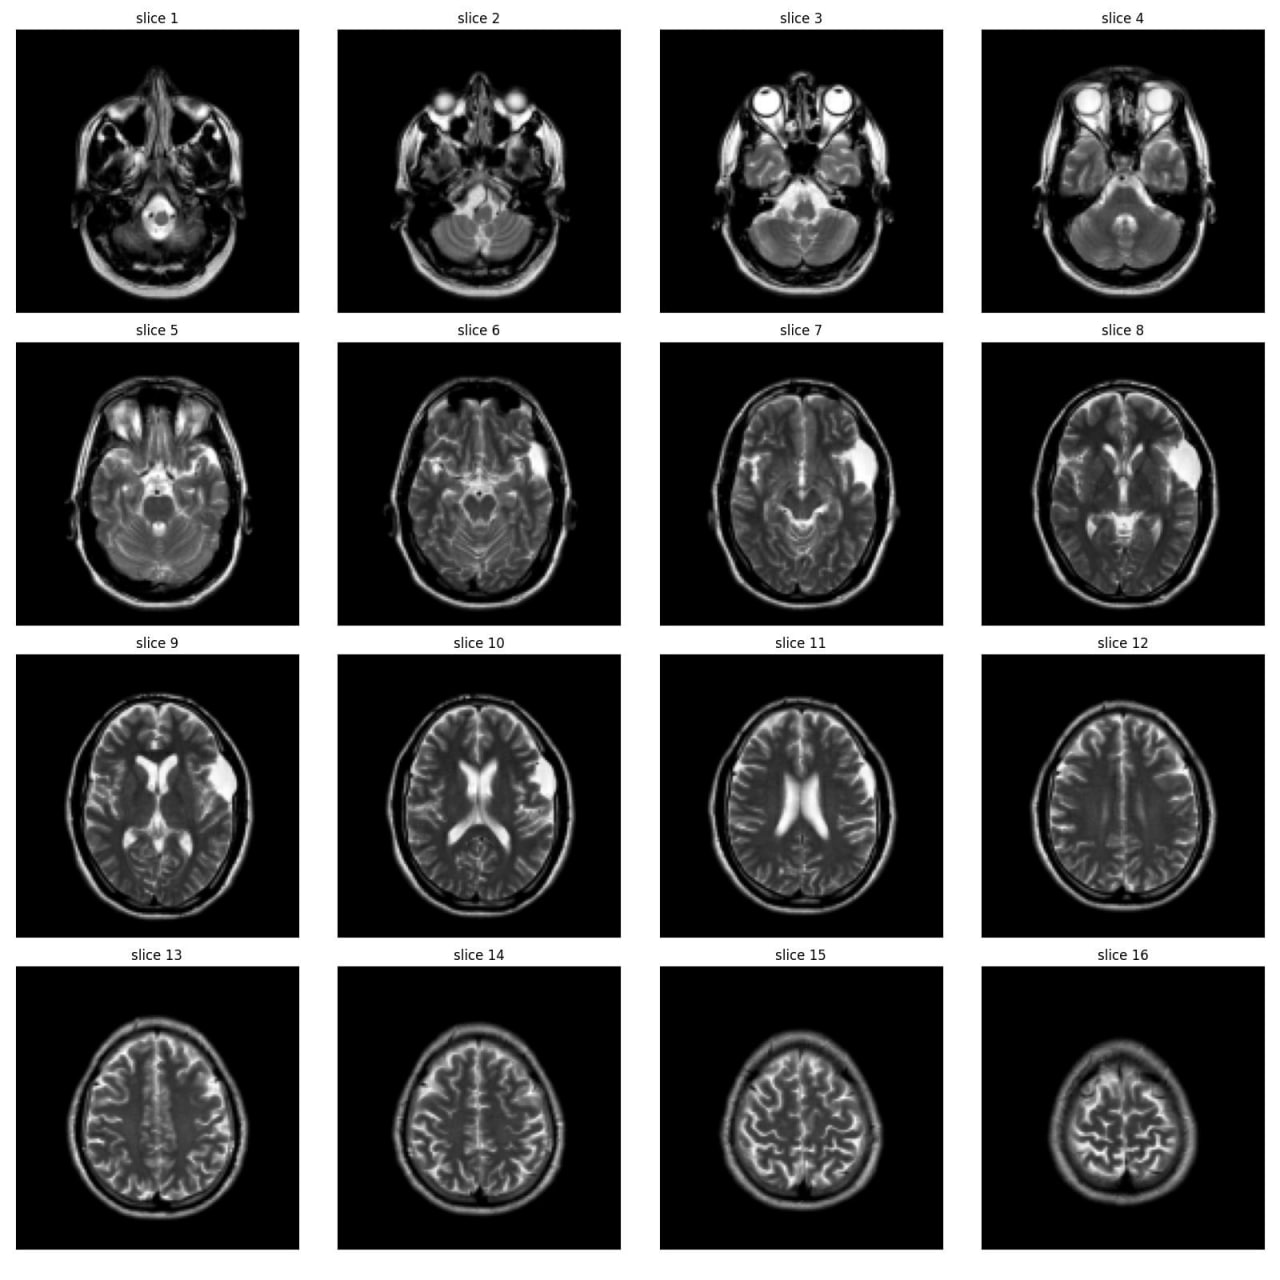

Abnormality Classification in Brain MRI

As part of the JIM3 team, I competed in the IAAA competition, which involved a dataset of 4,000 MRI images, with only 500 labeled as abnormal. The competition aimed to develop a model for patient-level abnormality classification. We utilized various models, including EfficientNet, DenseNet, ResNet, custom CNN models, and Vision Transformers (VIT), along with different preprocessing techniques. Working closely with a medical team, we converted subject-level annotations into slice-level annotations for more effective model training. Despite discovering inconsistencies in the test set and normal cases after the competition, we secured 17th place among over 100 teams. The technical team is currently working on a paper using the annotated data from this project.